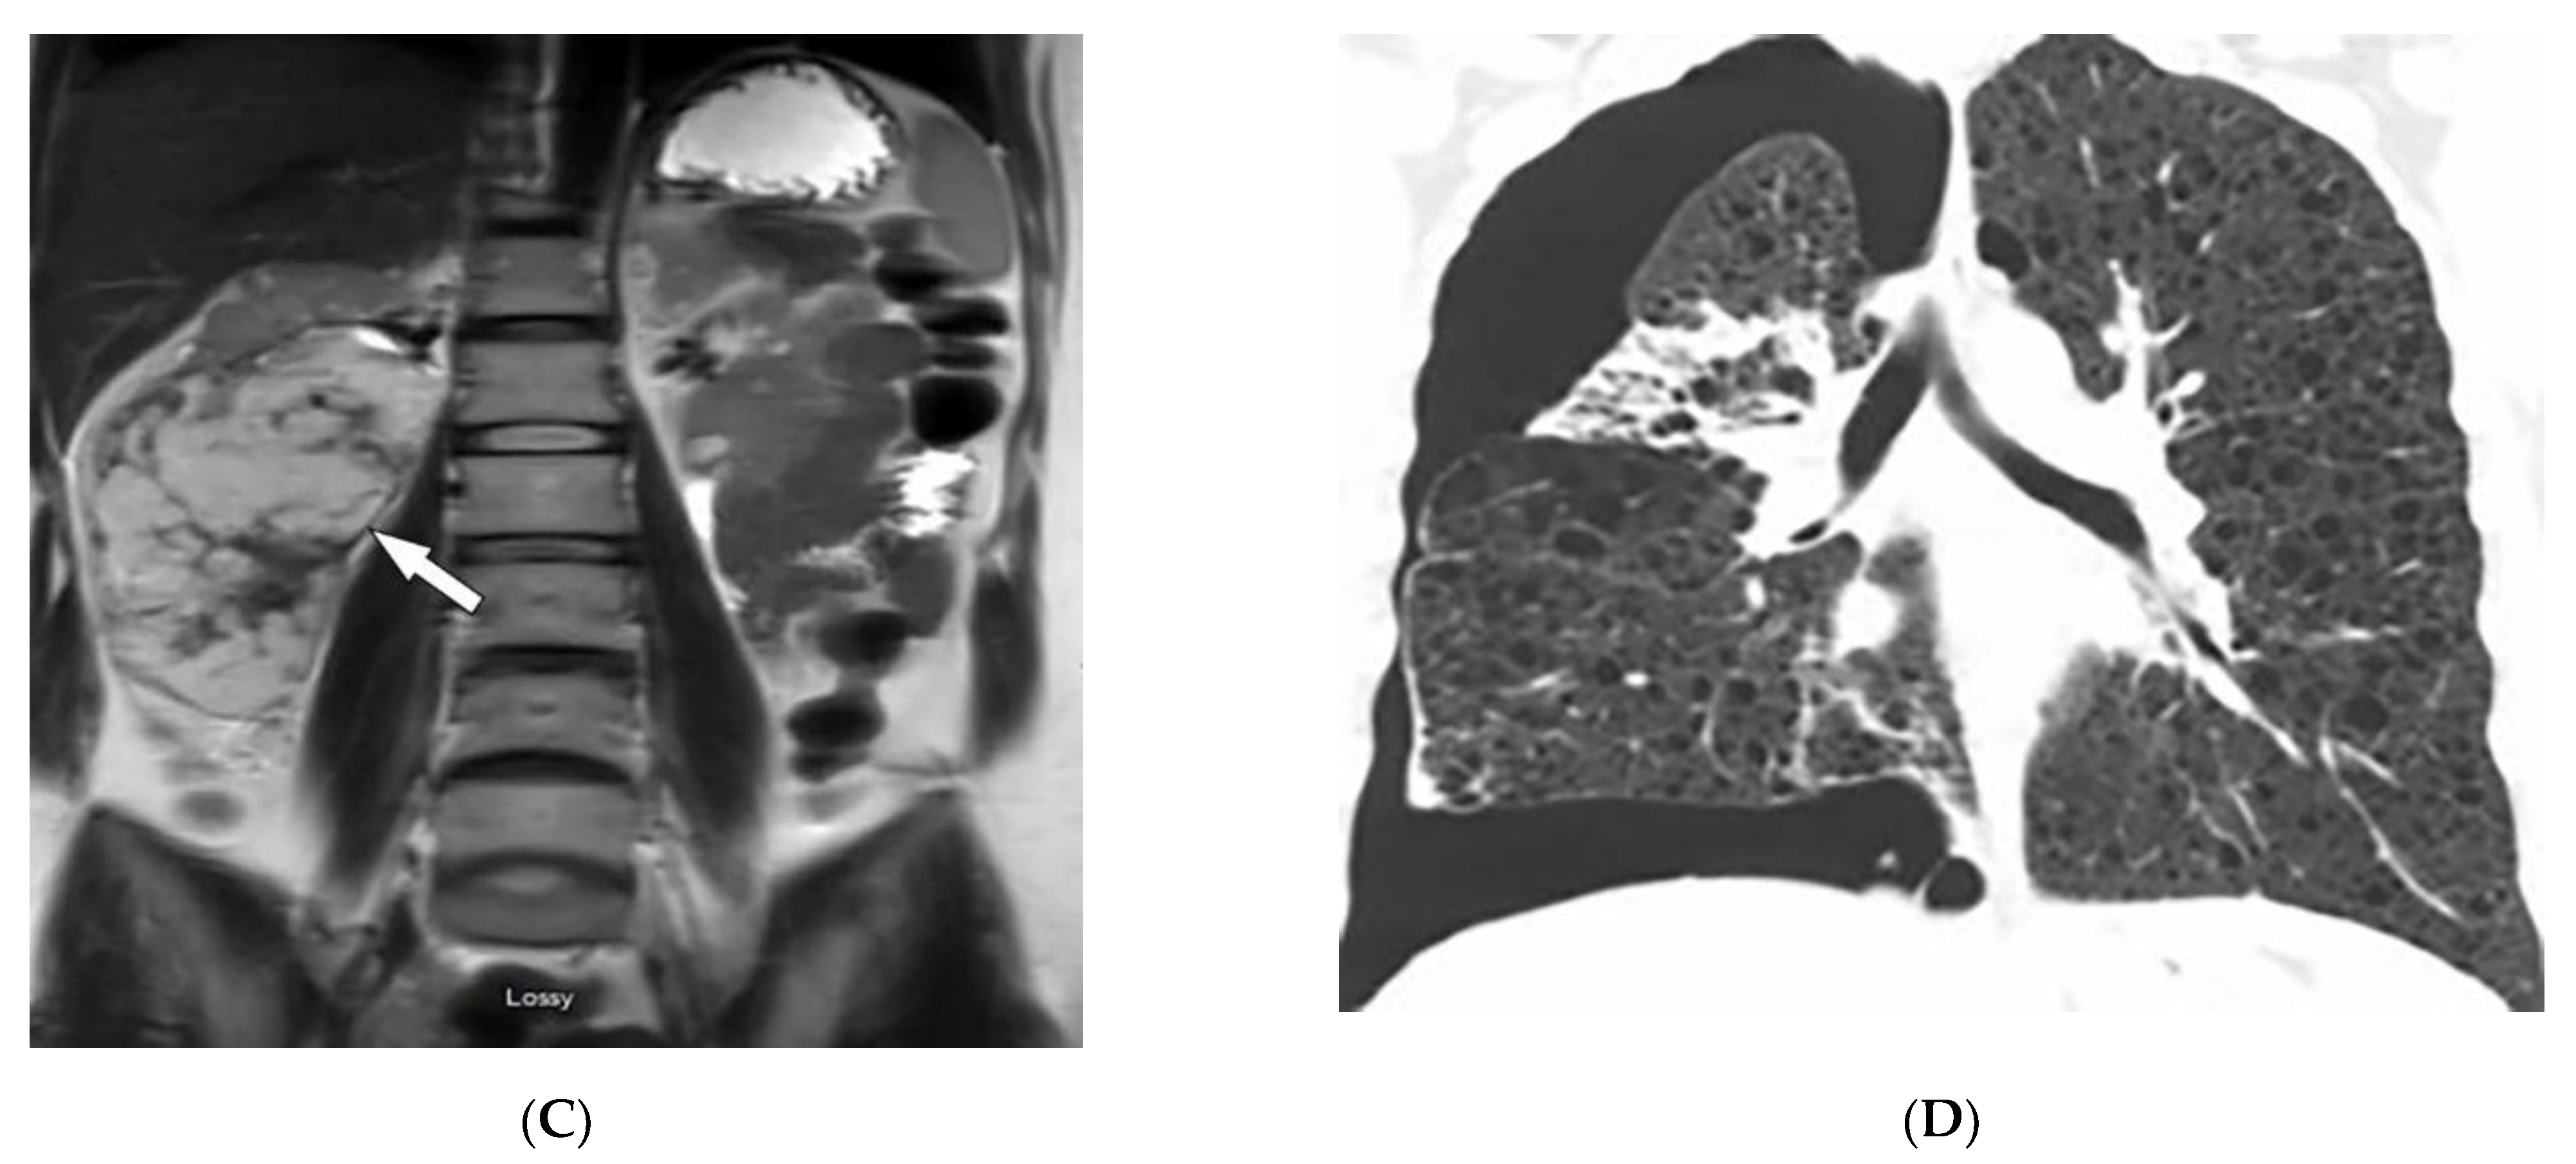

4.2. Kaposi Sarcoma

| Kaposi sarcoma | Erythematous or violaceous macules, plaques, nodules Pulmonary involvement Gastrointestinal involvement | Nodular enhancing masses Peribroncovascular nodules and halo sign |